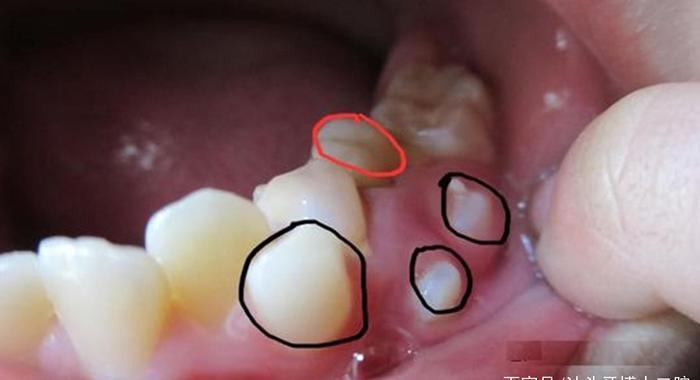

另外,有些智齿不能正常萌出,埋在牙龈下面,从口腔外部是看不出来的,只有拍摄口腔CT才能看到,这也会被误以为是不长智齿。